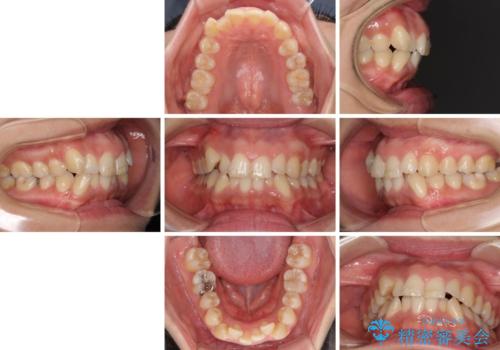

- 上下前歯のデコボコを気にして来院された患者様です。

デコボコが強いため、非抜歯で矯正をすると出っ歯仕上がりとなるため、上下左右の第一小臼歯4本を抜歯することとしました。

前歯のデコボコを短期間で解消 ワイヤー装置による抜歯矯正